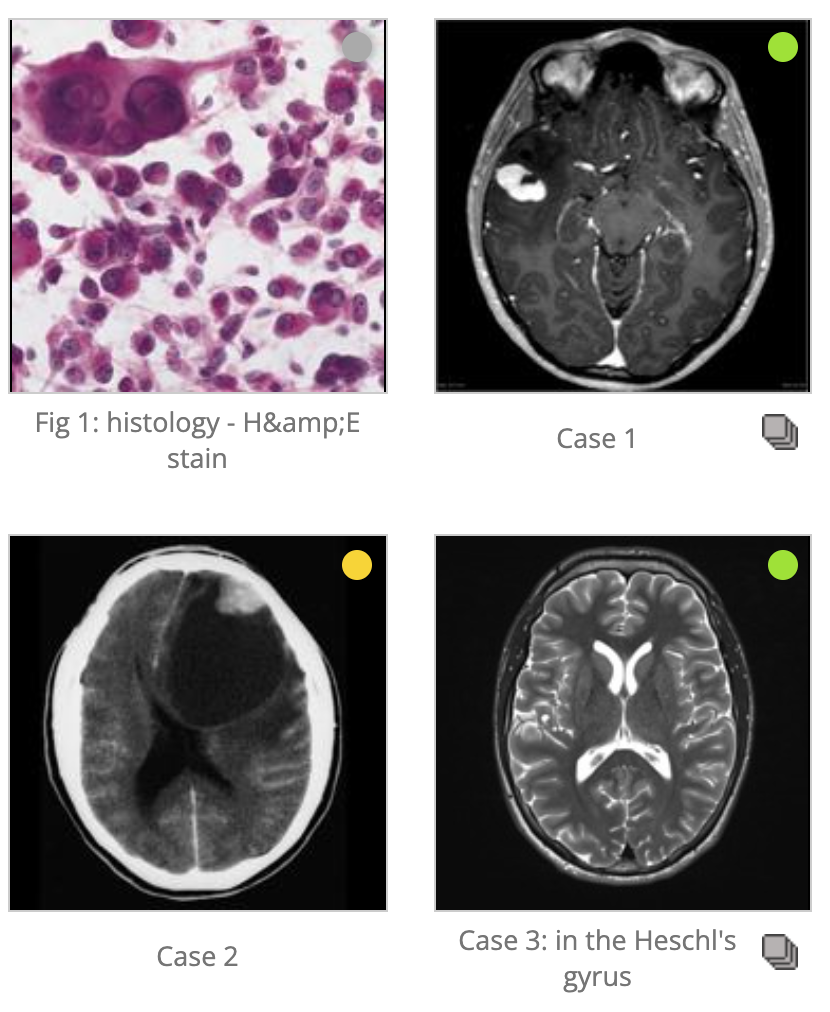

Primary brain tumors that can be multifocal

Cortically based tumors

PDOG

Pleomorphic Xanthroastrocytoma (PXA)

https://radiopaedia.org/articles/pleomorphic-xanthoastrocytoma

DNET (Dysembroplastic Neuroepitheilal Tumor)

Oligodendroglioma

Ganglioglioma